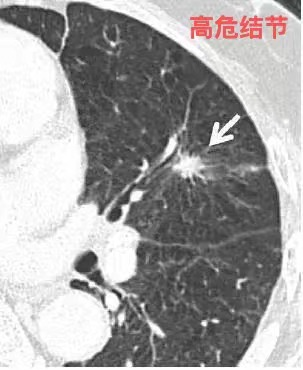

肺癌高危结节